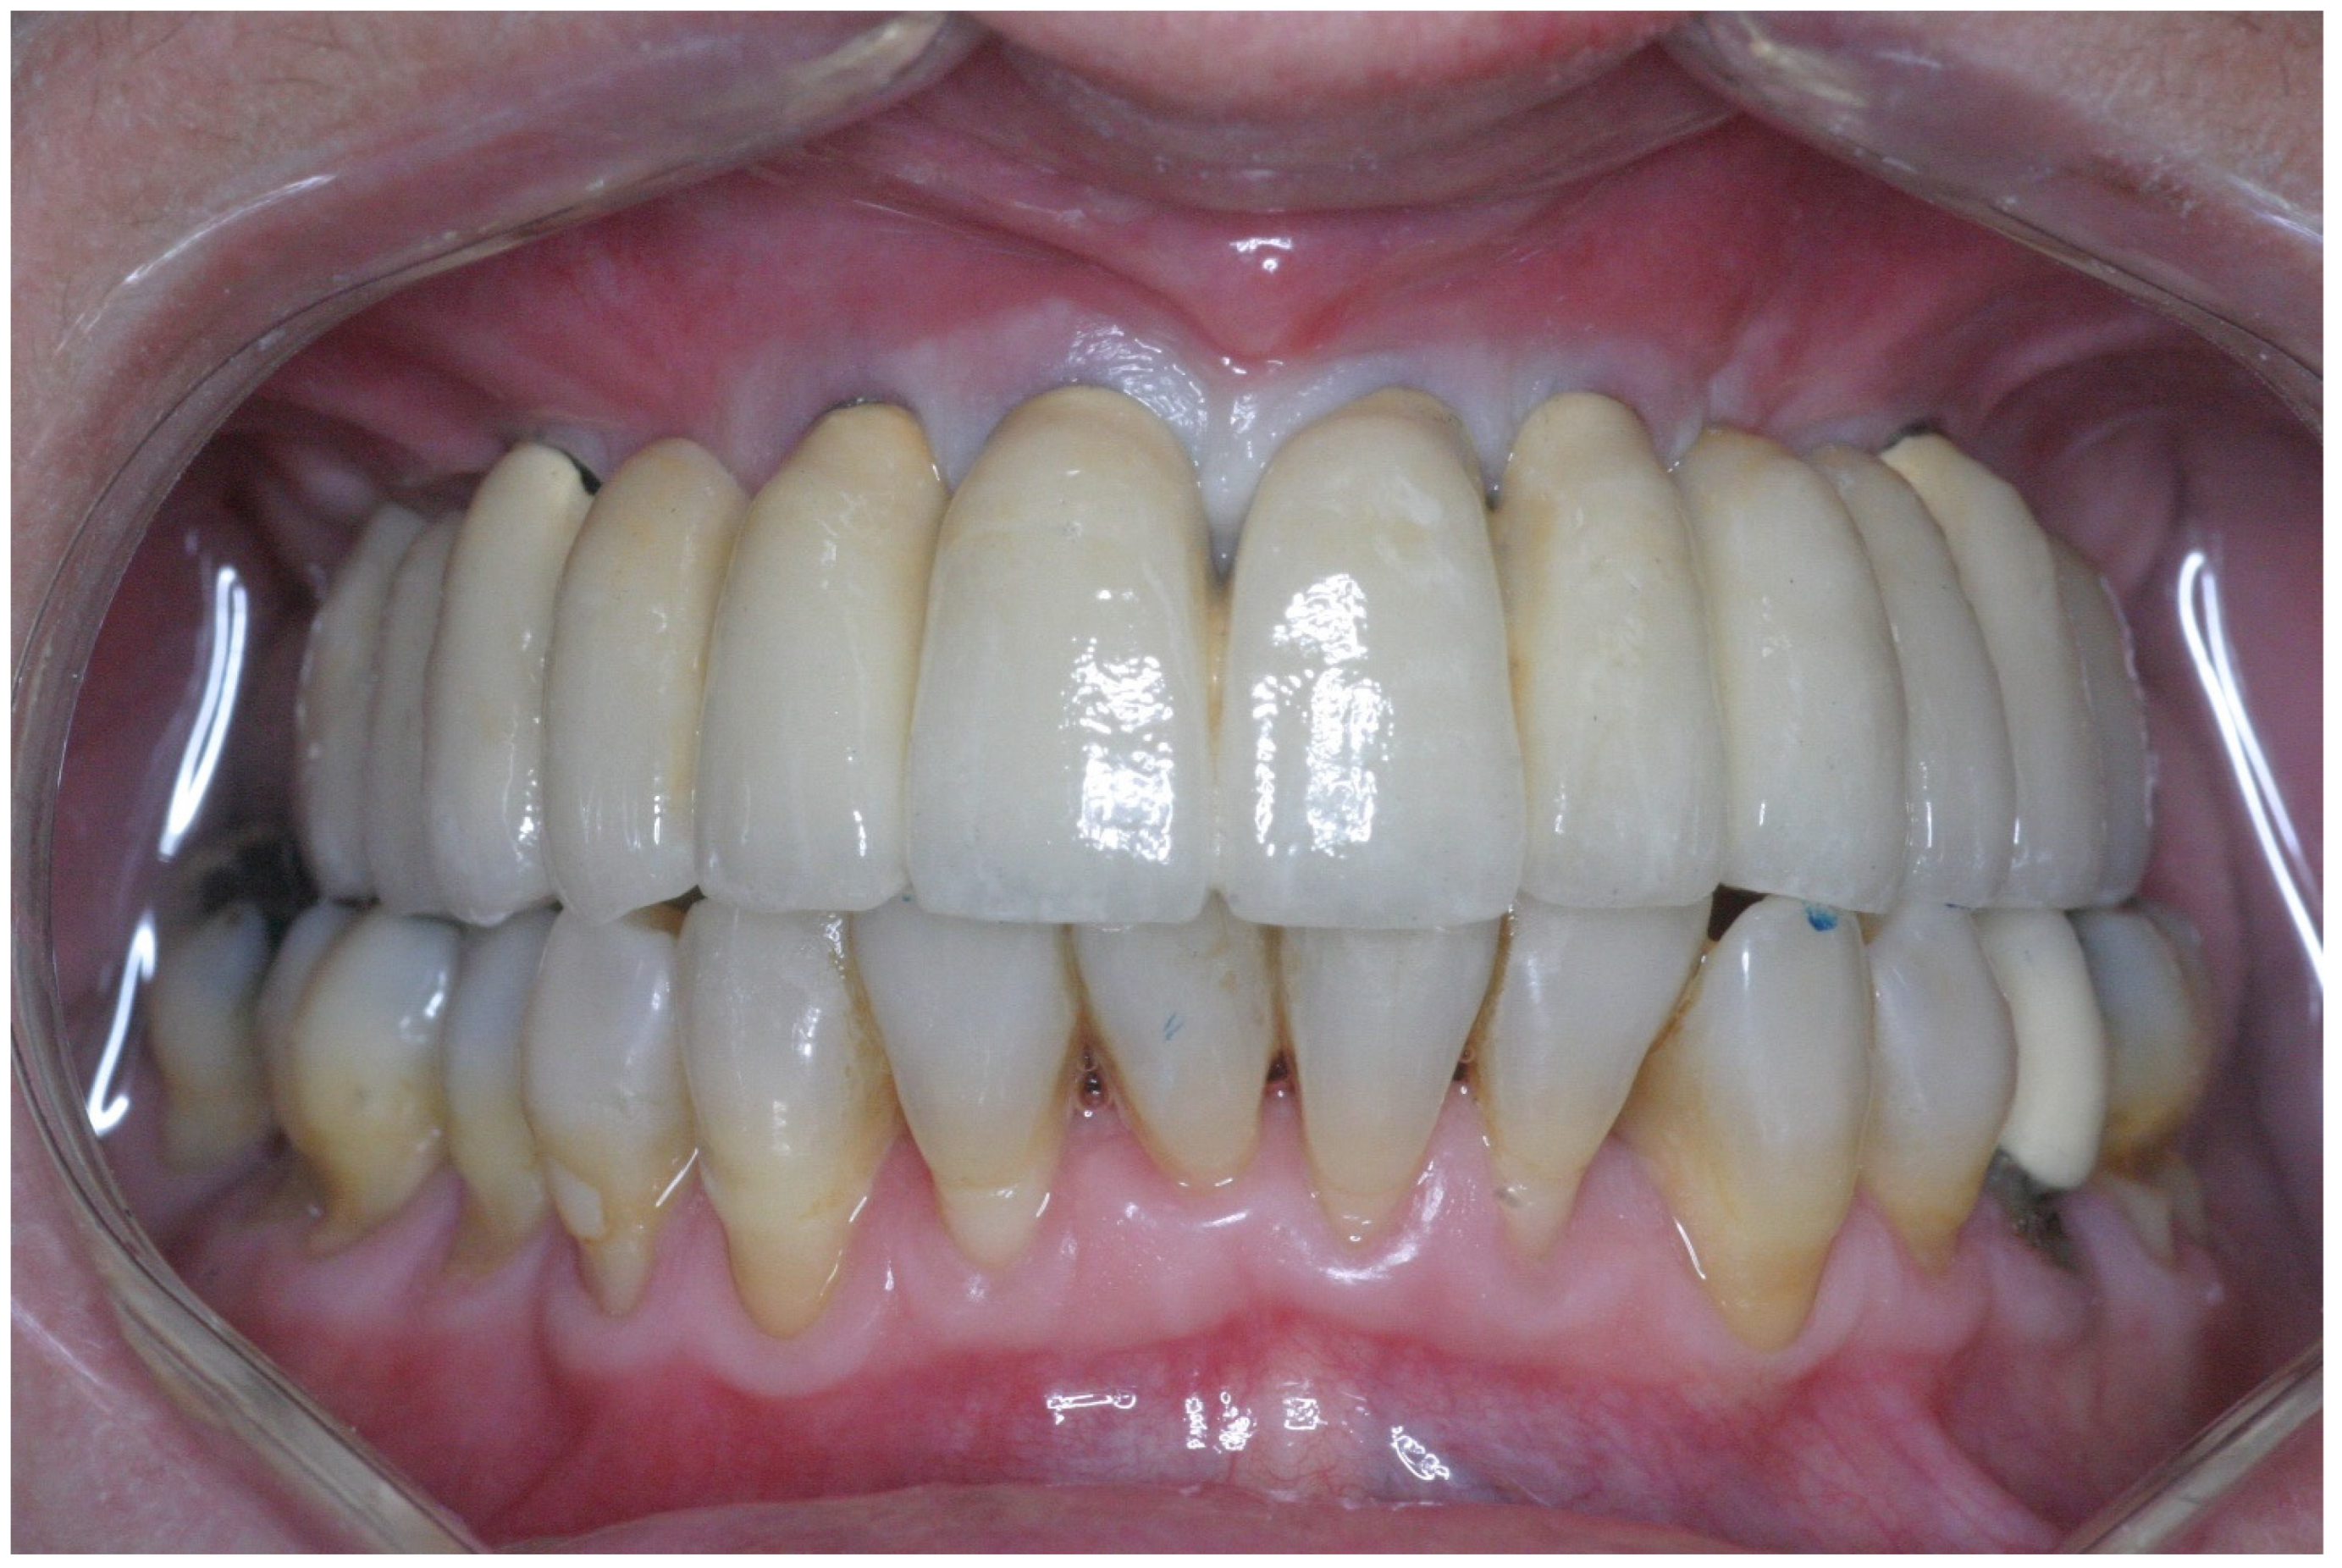

2.3. Prosthetic Protocol

3.2. Implant Survival and Success Rate